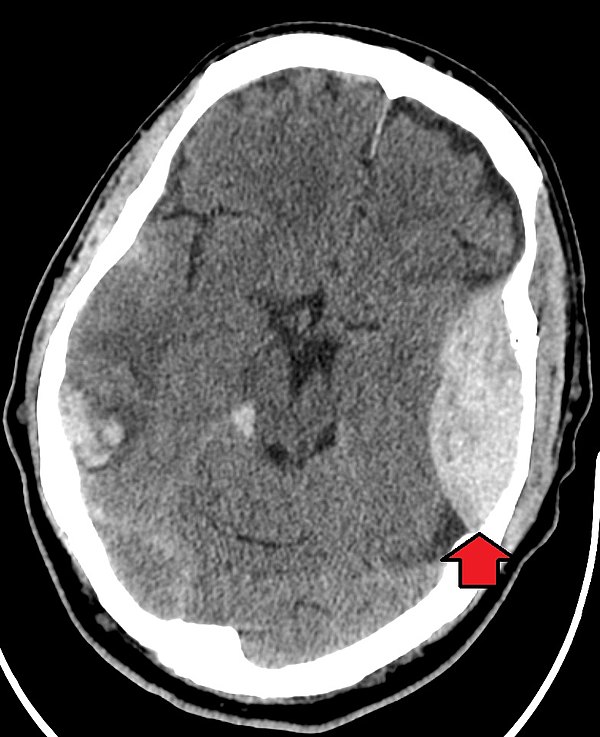

Example 1

Take a look at the following example. Let us go through how we would systematically analyse this and the diagnosis.

D – This is a CT Head taken on ….., of the following patient….. Is there a previous CT scan to compare to?

“On initial inspection, there appears to be an intracranial bleed, but I will proceed to go through it systematically.”

B – Looking at the film, there is a convex shaped density in the left side over the pterion. This is indicative of an extradural bleed.

C – The cisterns are clear and no sing of a subarachnoid haemorrhage.

B – The appears to me slight shifting of the brain tissue across the midline to the right. There is no area of hypo/hyperdensity and no obvious masses or ring-enhancing lesions.

V – The ventricles are not enlarged and there is no signs of an intraventricular bleed.

B – There appears to be damage to the skull over the left pterion.

Diagnosis

Extradural Haematoma